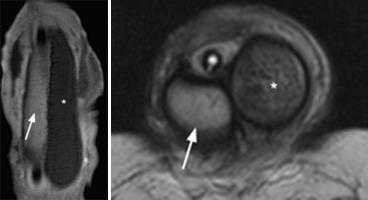

Нормальные яички. МРТ: (а) Аксиальное Т2-взвешенное изображение. Нормальная интенсивность сигнала от яичек; (b) Сагиттальное Т1 -взвешенное изображение после внутривенного введения контрастного вещества. Сигнал средней интенсивности от яичка. Нормальный хвост придатка (стрелка).

Что покажет МРТ при нормальной мошонке

- гомогенный сигнал средней интенсивности на Т1-взвешенном изображении

- Высокая интенсивность сигнала на Т2-взвешенном изображении

- Гипоинтенсивная перегородка идет радиально от капсулы к средостению яичка

- Белочная оболочка: тонкая линия с низкой интенсивностью сигнала

- изоинтенсивный по сравнению с яичками на Т1- взвешенном, гипоинтенсивный на Т2-взвешенном изображении

- более выраженное контрастное усиление по сравнению с яичками.